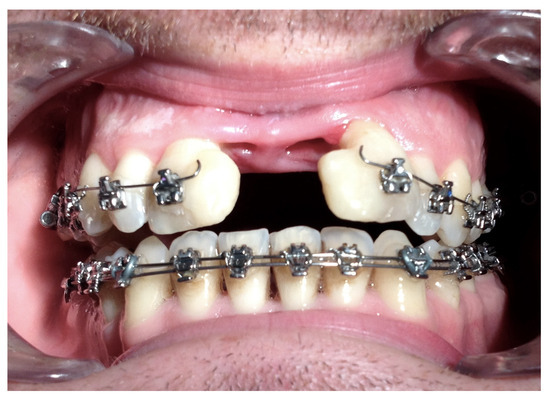

| No possibility of distraction—1 case | Maxillary incisor root resorption—2 cases |

| Perforation of the maxillary alveolar process caused by the distractor—1 case | Maxillary incisor necrosis—2 cases |